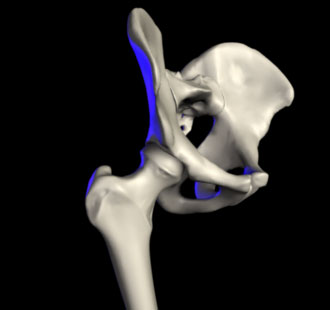

In anatomy, the hip is the bony projection of the femur which is known as the greater trochanter, and the overlying muscle and fat. The hip joint, scientifically referred to as the acetabulofemoral joint, is the joint between the femur and acetabulum of the pelvis and its primary function is to support the weight of the body in both static (e.g. standing) and dynamic (e.g. walking or running) postures.

تشريح مفصل الورك